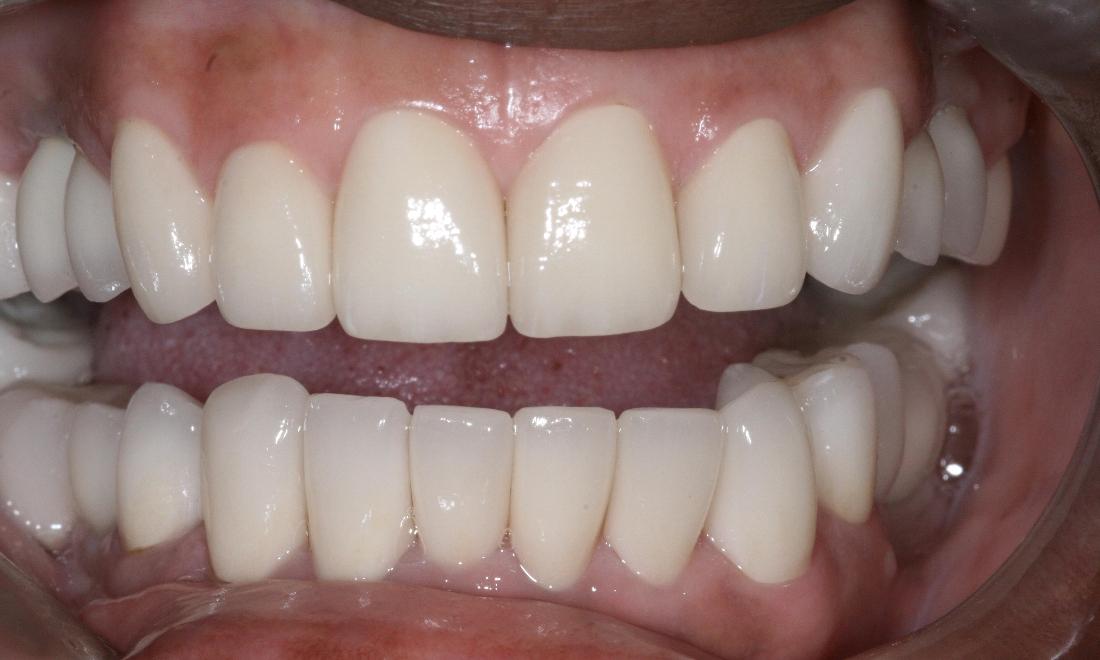

Above all, we are committed to offering and delivering exceptional, comprehensive dental care to each and every one of our clients. Through a unique mix of ultra-contemporary office design elements; the finest dental technologies, materials, and treatments; and a strong emphasis on exemplary customer service, it is our mission to create a practice environment which fosters the highest level of patient comfort safety, and overall satisfaction. We strive to protect the health of our patients and add beauty to their smiles. We will not be satisfied until we have perfected THE ultimate experience - one that includes Five Star service, extraordinary dentistry and makes a positive, lasting impression on the lives of our patients.